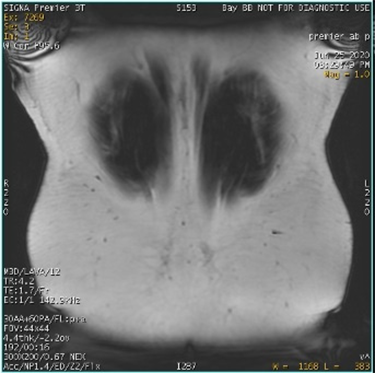

| Fat/Water Swap Areas that should appear fat suppressed are water suppressed, and ar-eas that should appear water suppressed are fat suppressed | ![]()

| Decreased linearity at the corners of the FOV corrupt the signal. The fat water identification algorithm may become confused, which results in a full series fat/water image swap. Phase wrap in slice and phase direction also influence swaps. This error may occur in regions of high magnetic field variation, in spatially isolated tissue, and/or in images with low signal-to-noise ratios, due to: